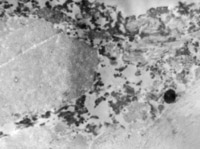

5-2-5 伤后第5天,,,,,,,胶原纤维相互融合,,,,,,,其间的细胞已崩解  TEM×6000